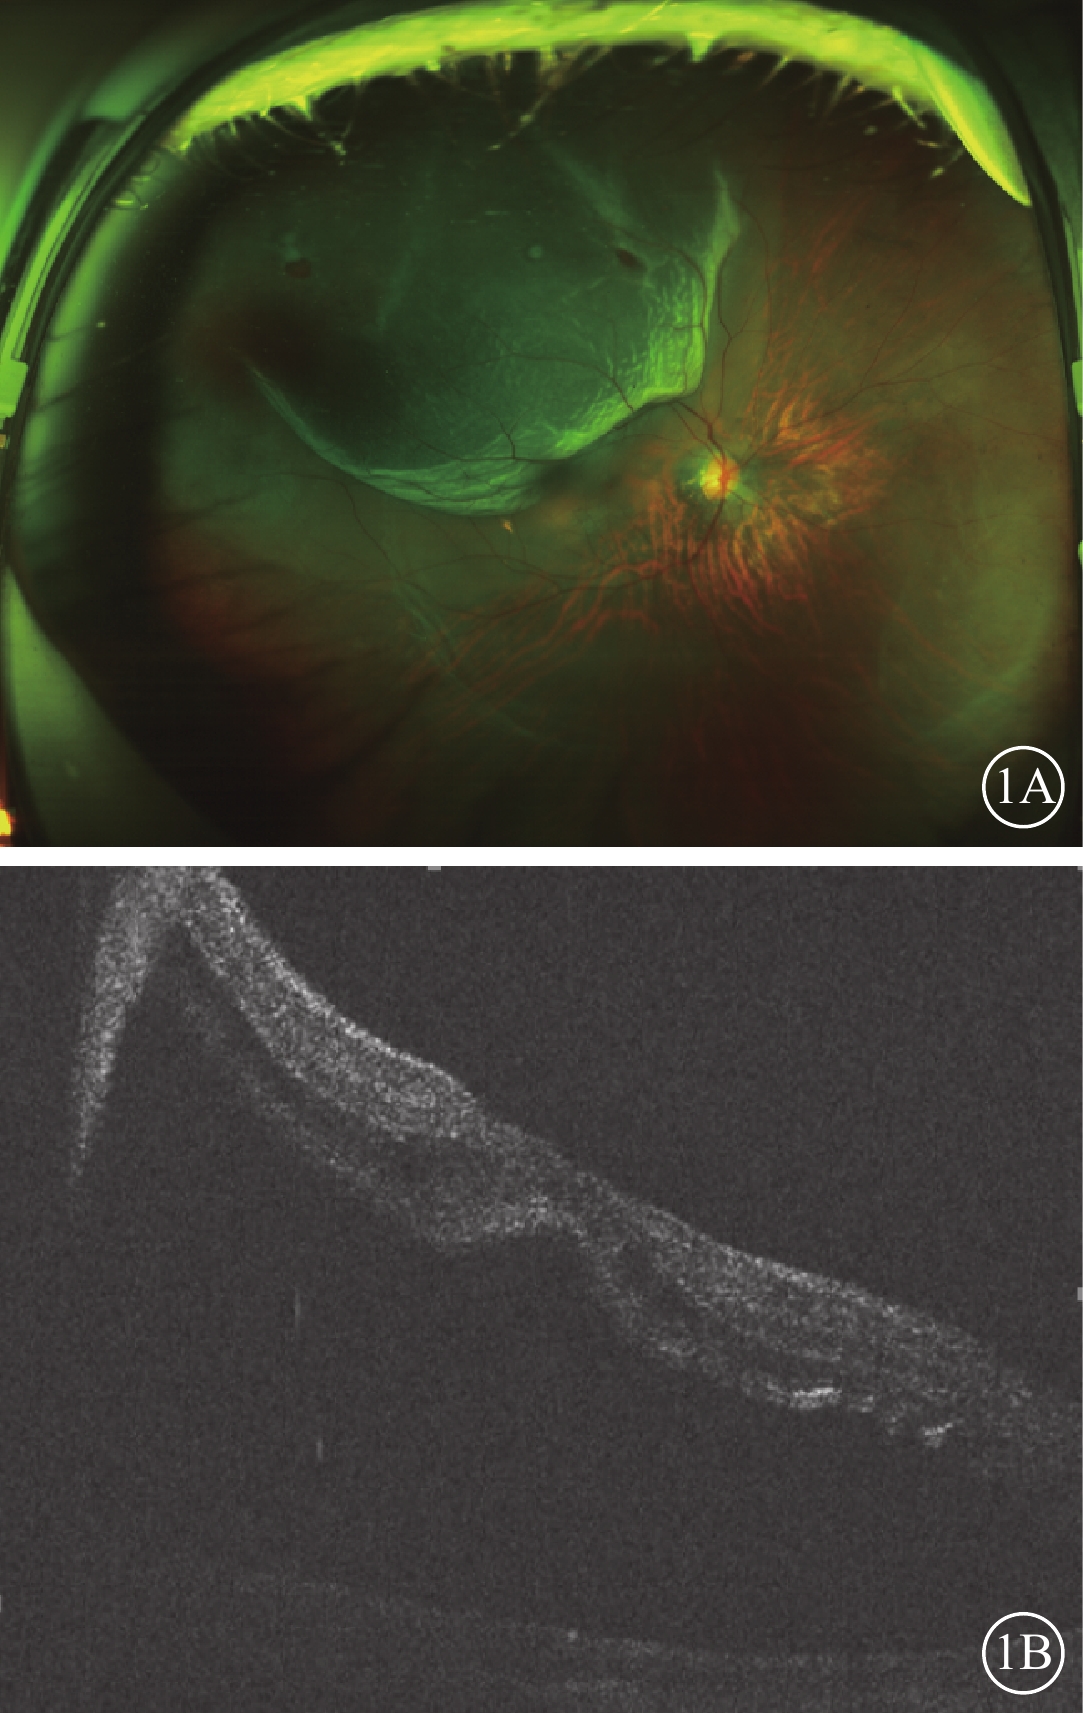

所有患眼行BCVA、眼壓、眼部B型超聲、雙目間接檢眼鏡、OCT及掃描激光檢眼鏡(SLO)檢查。12只眼中,BCVA<0.1、0.1~0.4、>0.4各4只眼(33.33%)。眼壓<10 mmHg(1 mmHg=0.133 kPa)4只眼(33.33%),10~15 mmHg 5只眼(41.67%),>15 mmHg 3只眼(25.00%)。視網膜脫離范圍累及1個象限(圖1A)3只眼(25.00%),累及2個象限7只眼(58.33%),累及3、4個象限各1只眼(8.33%)。視網膜脫離已累及黃斑(圖1B)8只眼(66.67%)。視網膜裂孔位于顳上方7只眼(58.33%),位于顳下方3只眼(25.00%),位于鼻上方2只眼(16.67%)。裂孔為小圓孔8只眼(66.67%),馬蹄樣裂孔3只眼(25.00%),不規則裂孔1只眼(8.33%)。PVR A級4只眼(33.33%),B級6只眼(50.00%),C1級2只眼(16.67%)。正視眼 2只眼(16.67%),近視眼10只眼(83.33%)。屈光度-3.00~-6.00 D 1只眼(8.33%);>-6.00 D 9只眼(75.00%)。

圖1

患眼手術前SLO及OCT像。1A示SLO像,可見右眼顳上方視網膜呈青灰色隆起,隆起區可見兩個小圓孔;1B示OCT像,可見黃斑區神經上皮脫離

圖1

患眼手術前SLO及OCT像。1A示SLO像,可見右眼顳上方視網膜呈青灰色隆起,隆起區可見兩個小圓孔;1B示OCT像,可見黃斑區神經上皮脫離

所有患眼行BCVA、眼壓、眼部B型超聲、雙目間接檢眼鏡、OCT及掃描激光檢眼鏡(SLO)檢查。12只眼中,BCVA<0.1、0.1~0.4、>0.4各4只眼(33.33%)。眼壓<10 mmHg(1 mmHg=0.133 kPa)4只眼(33.33%),10~15 mmHg 5只眼(41.67%),>15 mmHg 3只眼(25.00%)。視網膜脫離范圍累及1個象限(圖1A)3只眼(25.00%),累及2個象限7只眼(58.33%),累及3、4個象限各1只眼(8.33%)。視網膜脫離已累及黃斑(圖1B)8只眼(66.67%)。視網膜裂孔位于顳上方7只眼(58.33%),位于顳下方3只眼(25.00%),位于鼻上方2只眼(16.67%)。裂孔為小圓孔8只眼(66.67%),馬蹄樣裂孔3只眼(25.00%),不規則裂孔1只眼(8.33%)。PVR A級4只眼(33.33%),B級6只眼(50.00%),C1級2只眼(16.67%)。正視眼 2只眼(16.67%),近視眼10只眼(83.33%)。屈光度-3.00~-6.00 D 1只眼(8.33%);>-6.00 D 9只眼(75.00%)。

圖1

患眼手術前SLO及OCT像。1A示SLO像,可見右眼顳上方視網膜呈青灰色隆起,隆起區可見兩個小圓孔;1B示OCT像,可見黃斑區神經上皮脫離

圖1

患眼手術前SLO及OCT像。1A示SLO像,可見右眼顳上方視網膜呈青灰色隆起,隆起區可見兩個小圓孔;1B示OCT像,可見黃斑區神經上皮脫離